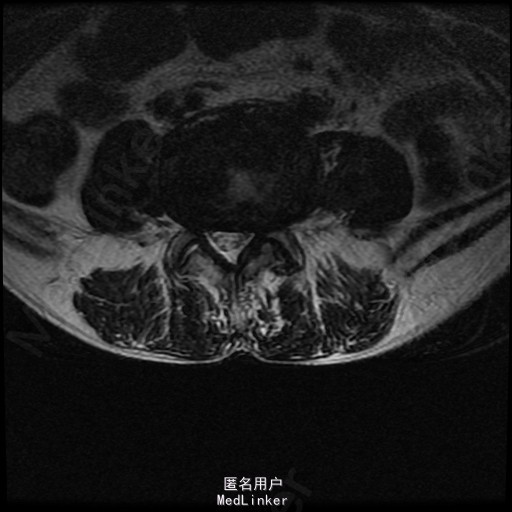

查体:左侧小腿外侧、足背感觉减退,右侧正常,双侧屈髋、伸膝、踝背伸肌肌力5级,左侧踇背伸、跖屈肌肌力4级,右侧踇背伸、跖屈肌肌力4-5级,双侧巴氏征阴性,直腿抬高试验左侧30°阳性,右侧阴性。 辅助检查: X-ray:腰椎退行性变,腰椎节段性性不稳 MR:腰椎间盘突出,腰3/4,4/5,腰4/5节段明显

诊断:腰椎椎管狭窄 处理: 1、完善相关辅助检查,明确诊断,有无手术指证; 2、完善手术评估,有无手术禁忌,手术风险及并发症; 3、在全麻下行腰椎后路减压,腰3/4左侧椎板减压,腰4/5椎间Cage植骨融合内固定术

随访 术后患者下肢麻木感觉较前好转,左侧踝背伸、跖屈肌力4级+,左侧肢体抬高试验阴性。术后MR检查减压彻底 讨论:1、腰椎椎管狭窄手术指证的把握,腰椎后路手术,腰椎椎间融合与椎板减压的选择? 2、术中探查如无明显间盘突出,以椎管骨性狭窄为主,可行腰椎后路椎板减压为主。